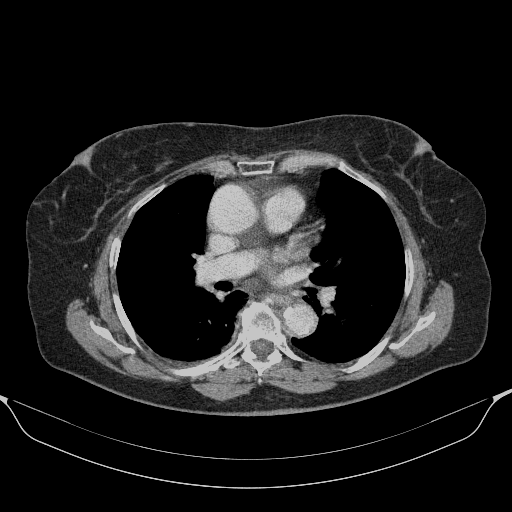

Generated VENOUS CT scan (A→B translation)

No window - Raw intensity values

Lung window (WL -600, WW 1500 β†’ Low βˆ’1350, High +150)

Mediastinum window (WL 40, WW 400 β†’ Low βˆ’160, High +240)